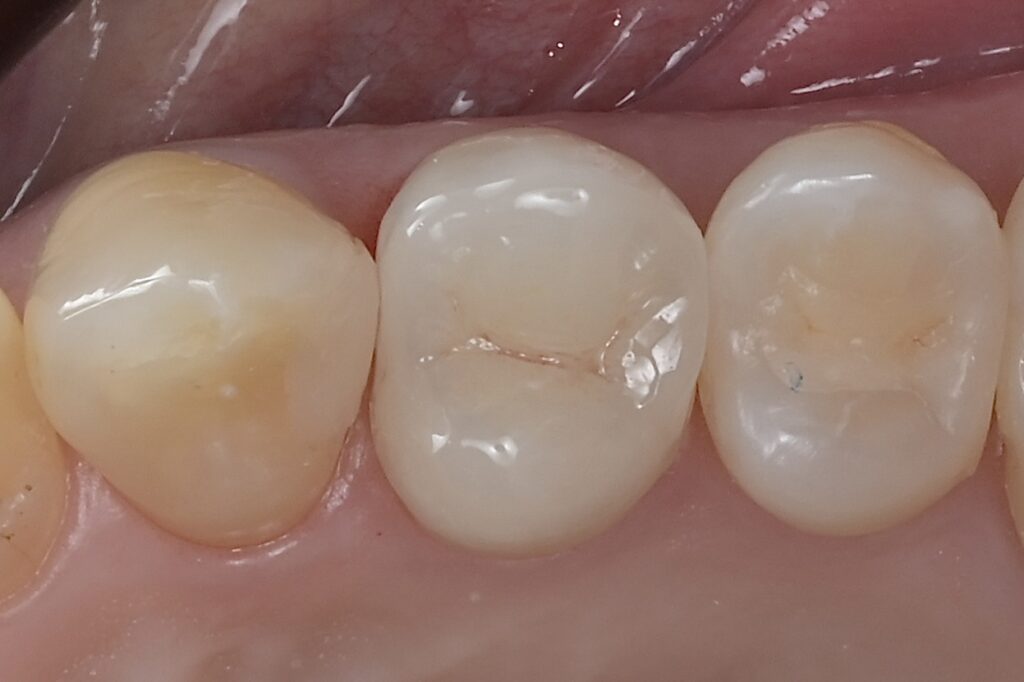

50代 虫歯治療 セラミック治療 e.maxテーブルトップ

07審美歯科

審美歯科では素材や手法を変えながら、審美的なアプローチを提案しています。見た目にコンプレックスがあると、自信を持ちづらくなることでしょう。そういった患者様一人ひとりの、口もとの印象を改善し人生が豊かになるようにしたいと考えています。審美治療を通し、その手助けをさせてください。